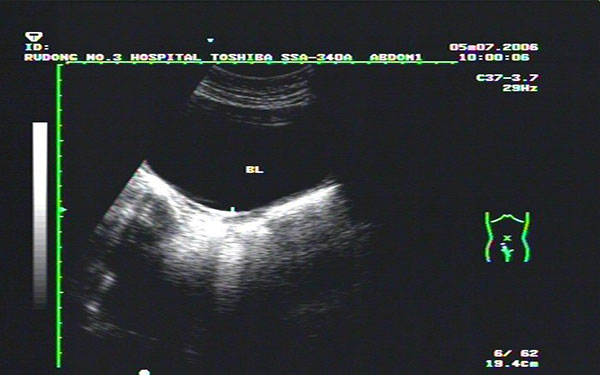

始基子宫诊断标准分享,超声出现这些内容就可确诊

始基子宫又称痕迹子宫。在胎儿发育时期,女性生殖器官由两侧副中肾管汇合而来,始基子宫系两侧副中肾管汇合后不久即停止发育所致,常合并无阴道。这种子宫极小,仅1~3厘米长,多无宫腔、无子宫内膜,无月经来潮。阴道四维彩超,可以清晰地看到始基子宫的影像,始基子宫很小,似一条索状,无宫腔波。始基子宫由于没有宫腔、没有子宫内膜,不会有月经来潮。始基子宫诊断标准始基子宫的诊断可依靠电子阴道镜,腔内四维彩超,染色体